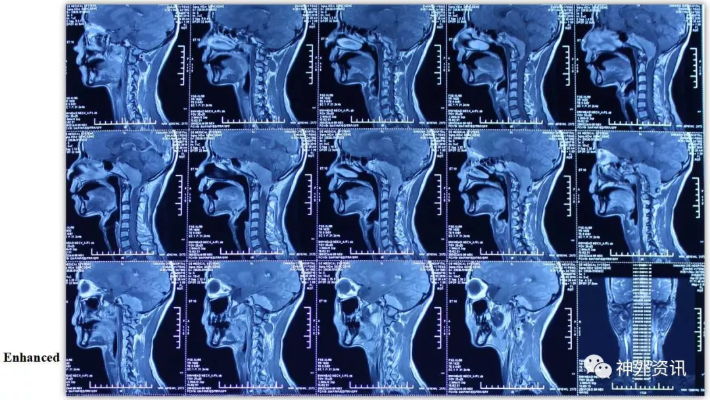

经乙状窦后联合远外侧入路切除岩斜-枕骨大孔-颈2脑膜瘤一例